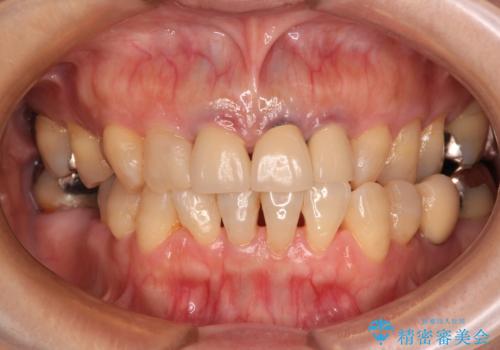

- 黄色みのある前歯のセラミックを、明るい色に替えたいとのことで来院された患者様です。

透明感がないことも気になっていたため、オールセラミッククラウンでは透けてしまう可能性のある金属の土台をファイバーコアに置き換え、1トーン明るいクラウンにて仕上げていくこととしました。